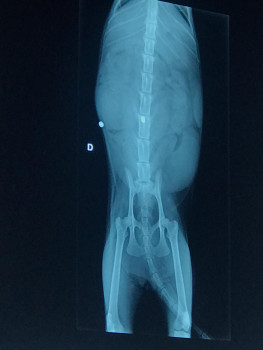

A gata foi socorrida, passou pelo veterinário Dr Erivaldo Nogueira no Hospital Medical Pet em Feira de Santana, fez exames de RX e ultra-som, que constatou a prenhez.

De acordo com o médico Dr Erivaldo, a bala que deixou a gata paraplégica atravessou a coluna e alojou dentro da lombar. A gata ganhou o nome de Nala, está se recuperando mas corre risco de sofrer uma hemorragia. Ela vai precisar fazer nos próximos dias novos exames de ultrassonografia, para em seguida fazer uma cesárea, pois devido o trauma ela não vai poder pari normal. A associação que está cuidando da gatinha, sobrevive de doações e atualmente sofre com a falta de recursos para manter os animais que moram no espaço.